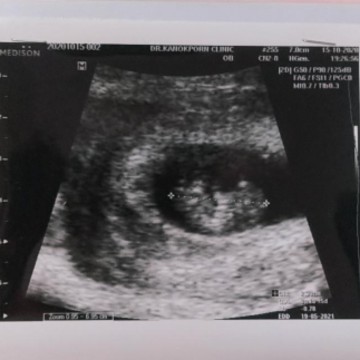

มีเห็นบ้างแล้วค่ะ7w5dแล้วค่ะ